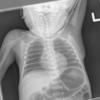

Normal neonate

Date: 02/07/2010

Views: 5856